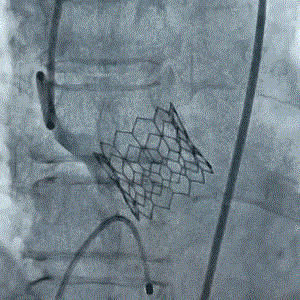

9月27日上午10时,直播开始,魏来教授团队耗时约1小时,经右侧股动脉植入23# Renatus介入主动脉瓣。瓣膜植入位置理想,功能表现出色,造影及经食道超声观察显示瓣膜无中央性返流,轻微瓣周漏,无冠脉血流受阻,无传导阻滞,主动脉瓣峰值流速降至2.0m/s,平均跨瓣压差降至7mm/Hg。手术取得圆满成功。

术前造影(见大量反流)                                   术后造影